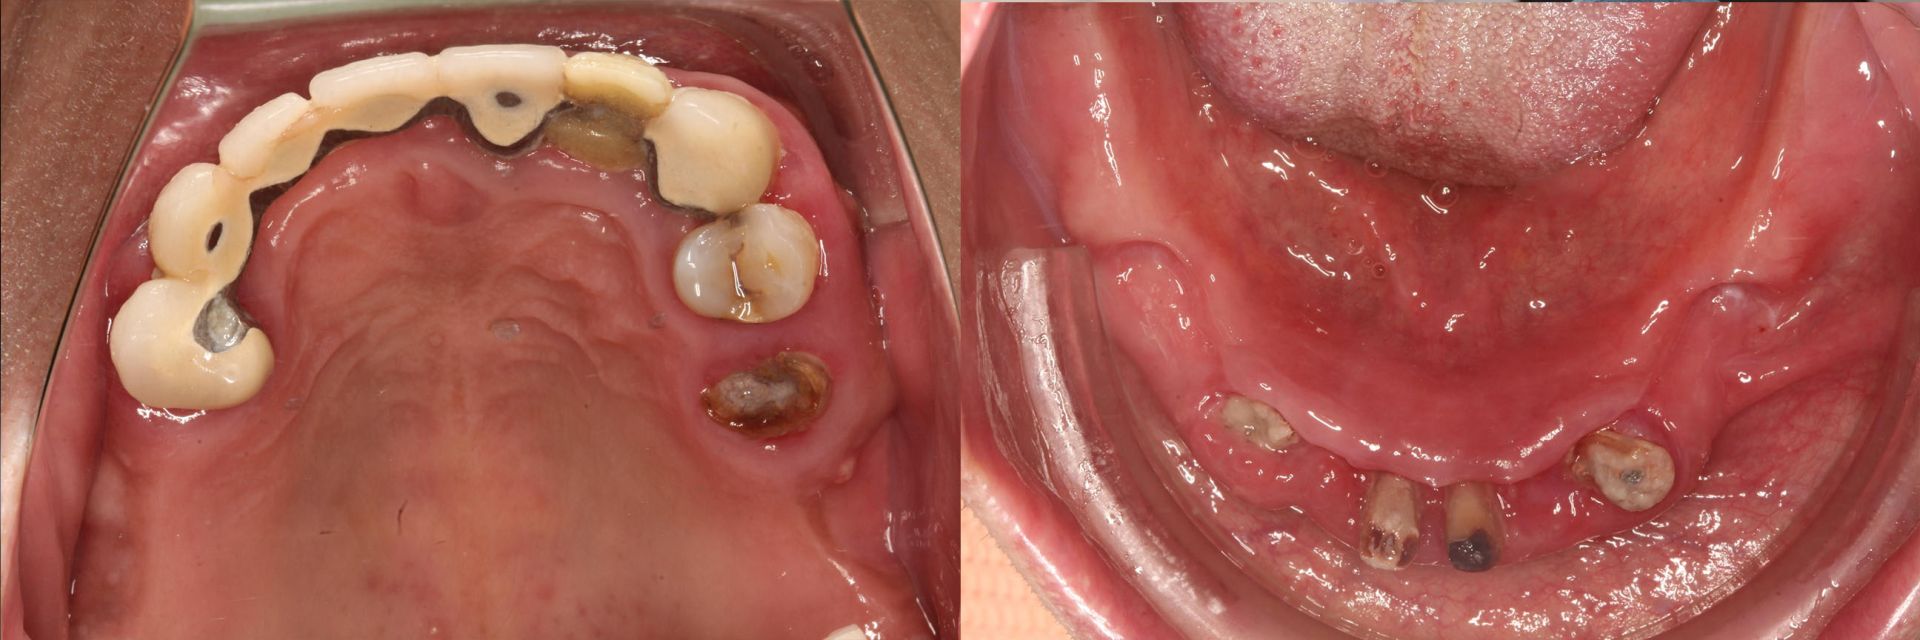

張先生是一位60歲的歌手,擁有多年的舞台經驗和無數次的掌聲,然而,這些榮耀背後,他卻一直隱藏著一個困擾他多年的秘密——他的牙齒問題。

早年的演出生活讓他忽略了對牙齒的保養,隨著年齡的增長,牙齒逐漸鬆動,甚至有幾顆已經快要離開他了,每次站在聚光燈下,他都擔心高音部分會不小心把牙齒噴出來,對他的表演造成影響。這種擔憂使他開始猶豫是否該進行植牙手術。

張先生找到了當代牙醫梁嘉元醫師和林宗佑醫師,兩位專業的牙醫師,開始了他植牙的旅程。一開始,他的確感到害怕和擔心。「還沒做過這種植牙,一下做全口重建會不會習慣?」他心中充滿疑問。然而,兩位醫師的細心分析和解釋讓他逐漸放鬆下來,並且整個治療過程也沒有給他帶來任何壓力。

All-on 4/6一日全口重建手術結束後,張先生從鏡子裡看著自己的新牙齒,感到了一種從未有過的自信。朋友們見到他,都驚訝於他的變化,「你的牙齒怎麼變那麼漂亮?」他笑著回答:「是嗎?以前沒有那麼漂亮嗎?」